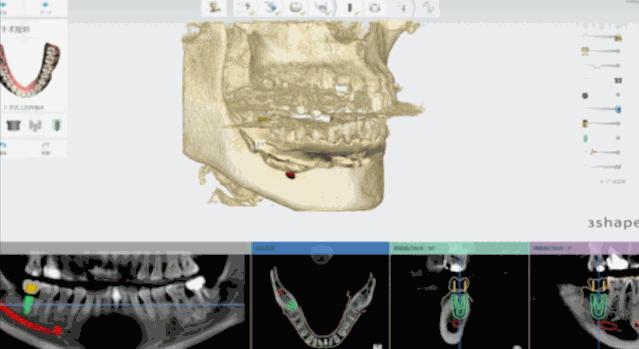

日照口腔医院种植中心配置先进的种植手术室,为患者提供各种类型的种植义齿修复,采用先进的医疗技术装备和种植系统,配备有丹麦3shape口内扫描仪、Yoshida激光治疗仪、卡瓦(KaVo)锥形束CT、超声骨刀等国际先进仪器和设备,装备有瑞士士卓曼等多套国际种植系统,同时配备设备先进的现代化消毒供应室,为疑难复杂病例的诊治提供了必要条件。

医院开展CAD/CAM数字化种植导板技术,通过整合数字化影像、cbct 数据以及数字化加工技术的新型种植导板,充分考虑到了颌骨条件、口腔解剖结构以及修复效果的结合,用以提高手术精度,降低手术风险,减轻患者痛苦。